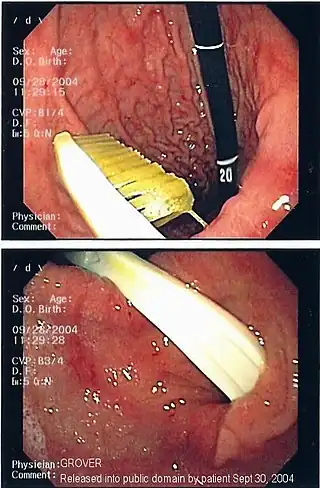

![]() Imagen endoscópica de un cuerpo extraño gástrico (cepillo de dientes) | ||

La presencia del cuerpo extraño se reconoce, de ordinario, a través de la exploración física, de un estudio de imagen o de una exploración endoscópica. Los estudios radiológicos sirven para visualizar y localizar los cuerpos extraños metálicos y radiopacos.